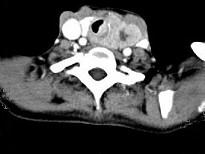

问题 女,50岁,左下颈部扪及一质硬、表面高低不平的包块,肿块逐渐增大,现感吞咽困难,CT如图所示,最可能诊断为()

选项 A.甲状腺癌 B.食管癌 C.喉癌 D.甲状腺原发淋巴瘤 E.颈部神经鞘瘤

答案 A